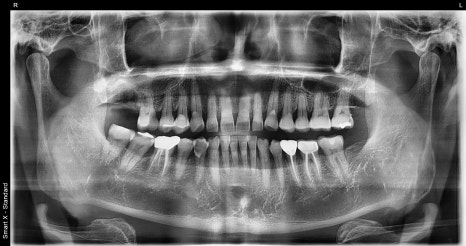

A detailed examination was carried out through panoramic imaging and CT scans.

The examination results showed not a simple cavity or crown fracture, but cracks extending to the root area.

If the crack extends to the root tip, it is difficult to save the tooth with conservative treatment,

and extraction followed by implant treatment should be considered.